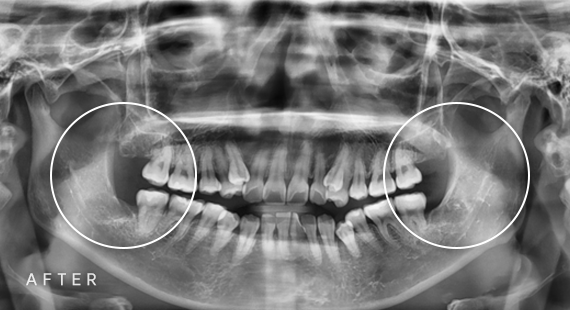

임플란트

충치치료

신경치료

사랑니 발치